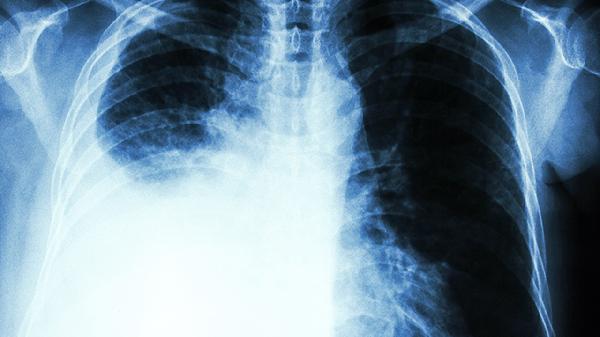

3、"拍胸片正常就没事"

早期肺癌在胸片上可能只是个小斑点。低剂量螺旋CT能发现0.5cm的结节,检出率是胸片的6倍。